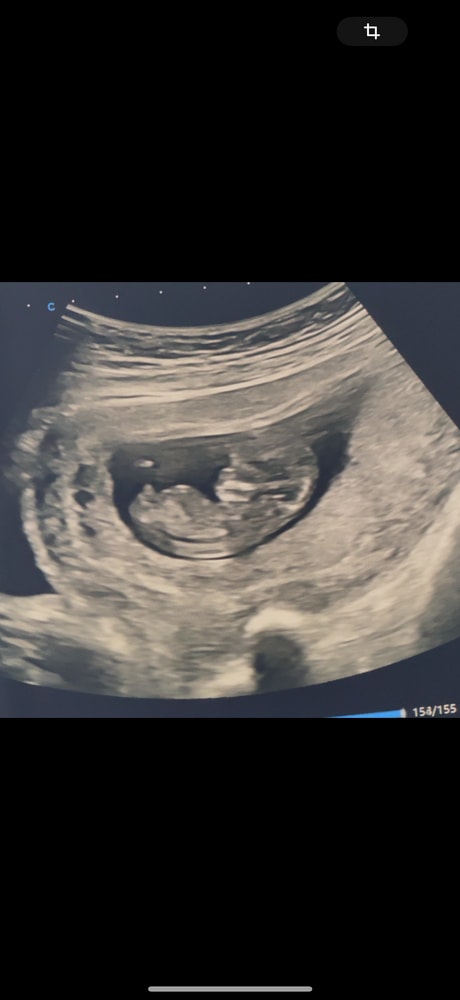

Половой орган мальчика? Не пуповина ли?))

это правда половой орган мальчика ?)

не пуповина или что-то другое?

Но сама узистка сказала и вот показала что мальчик скорее всего …Но 100 % не дала

у кого так торчал при Мальчике ?

Да, нам вчера доктор тоже показал этот бугорок, прямо точно как на второй фотке у вас, сказал это 100% мальчик. А пуповина она же на животе. Ее совсем по другому видно.